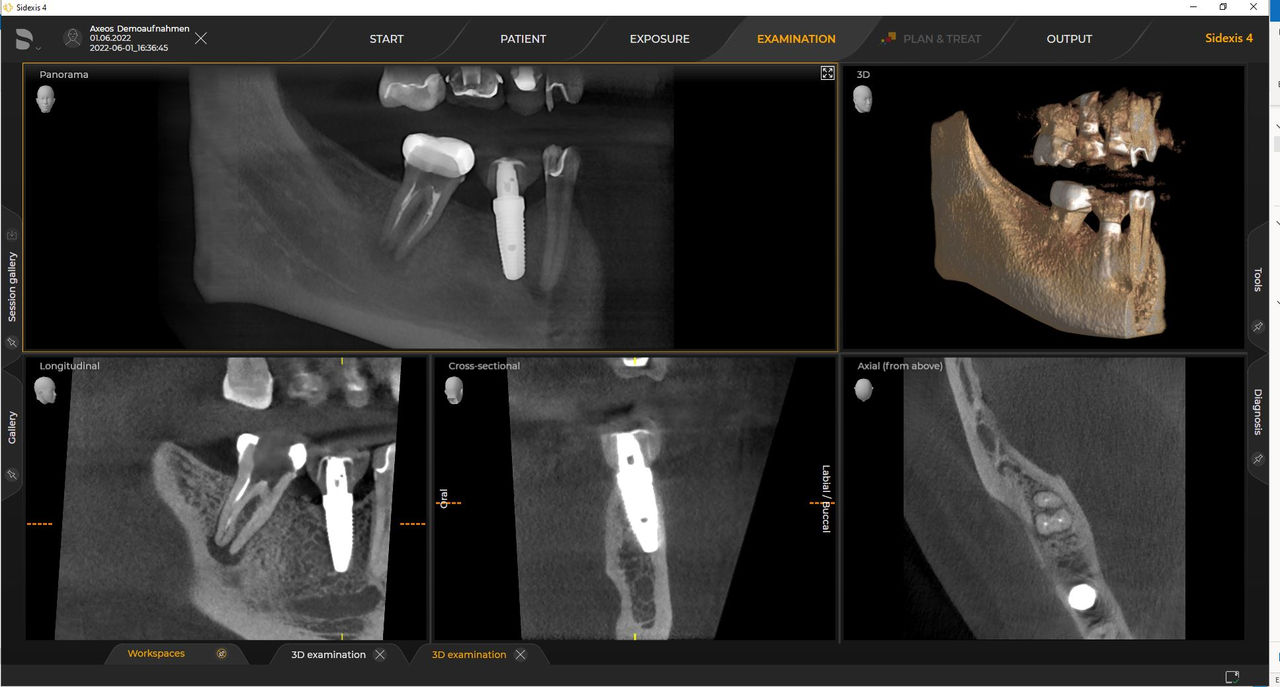

Las unidades 3D de Dentsply Sirona funcionan exclusivamente con Sidexis 4. Sin embargo, la migración de datos de Sidexis XG a Sidexis 4 es muy fácil. Sidexis 4 permite una experiencia digital completa con las últimas herramientas.